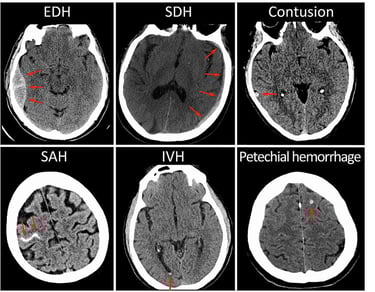

We are excited to announce the launch of our internal research collaboration with University Hospital L. Pasteur in Košice. This foundational project seeks to explore AI applications in diagnosing brain hemorrhages, a critical component in managing Traumatic Brain Injuries (TBIs).This project aims to lay the theoretical groundwork for AI models designed to support brain hemorrhage diagnosis. At TRL 1, our focus is on establishing foundational concepts and identifying the ways an AI model might assist in detecting and classifying different types of brain hemorrhages on CT scans in the future. TBIs are a leading cause of mortality and long-term disability globally. In the acute setting, brain hemorrhages resulting from TBIs require precise and timely diagnosis to guide life-saving interventions.

Traumatic brain injuries (TBI) are among the most severe global health challenges, often leading to permanent disabilities or fatal outcomes. The ability to deliver timely and accurate diagnosis is critical in shaping patient outcomes, as rapid intervention significantly improves survival and recovery chances. However, TBI diagnostic accuracy is frequently challenged by the demanding nature of emergency settings. Physicians must assess CT images under intense time pressure, where subtle signs of bleeding can be easily missed—especially in high-stress conditions like overnight shifts and after extended hours.

TRL 1 – Establishing a Conceptual Foundation:

In this early TRL 1 phase, our focus is theoretical, aiming to lay down a robust framework to assess AI's potential in enhancing TBI diagnosis. Working closely with clinical experts at L. Pasteur University Hospital, we are evaluating current diagnostic approaches and exploring AI’s role in supporting clinicians with “second read” capabilities, to reduce diagnostic variance. By thoroughly analyzing current AI methods and conceptualizing novel models, our goal is to validate AI’s potential to enhance diagnostic precision and reduce time to decision, particularly for critical and complex cases.